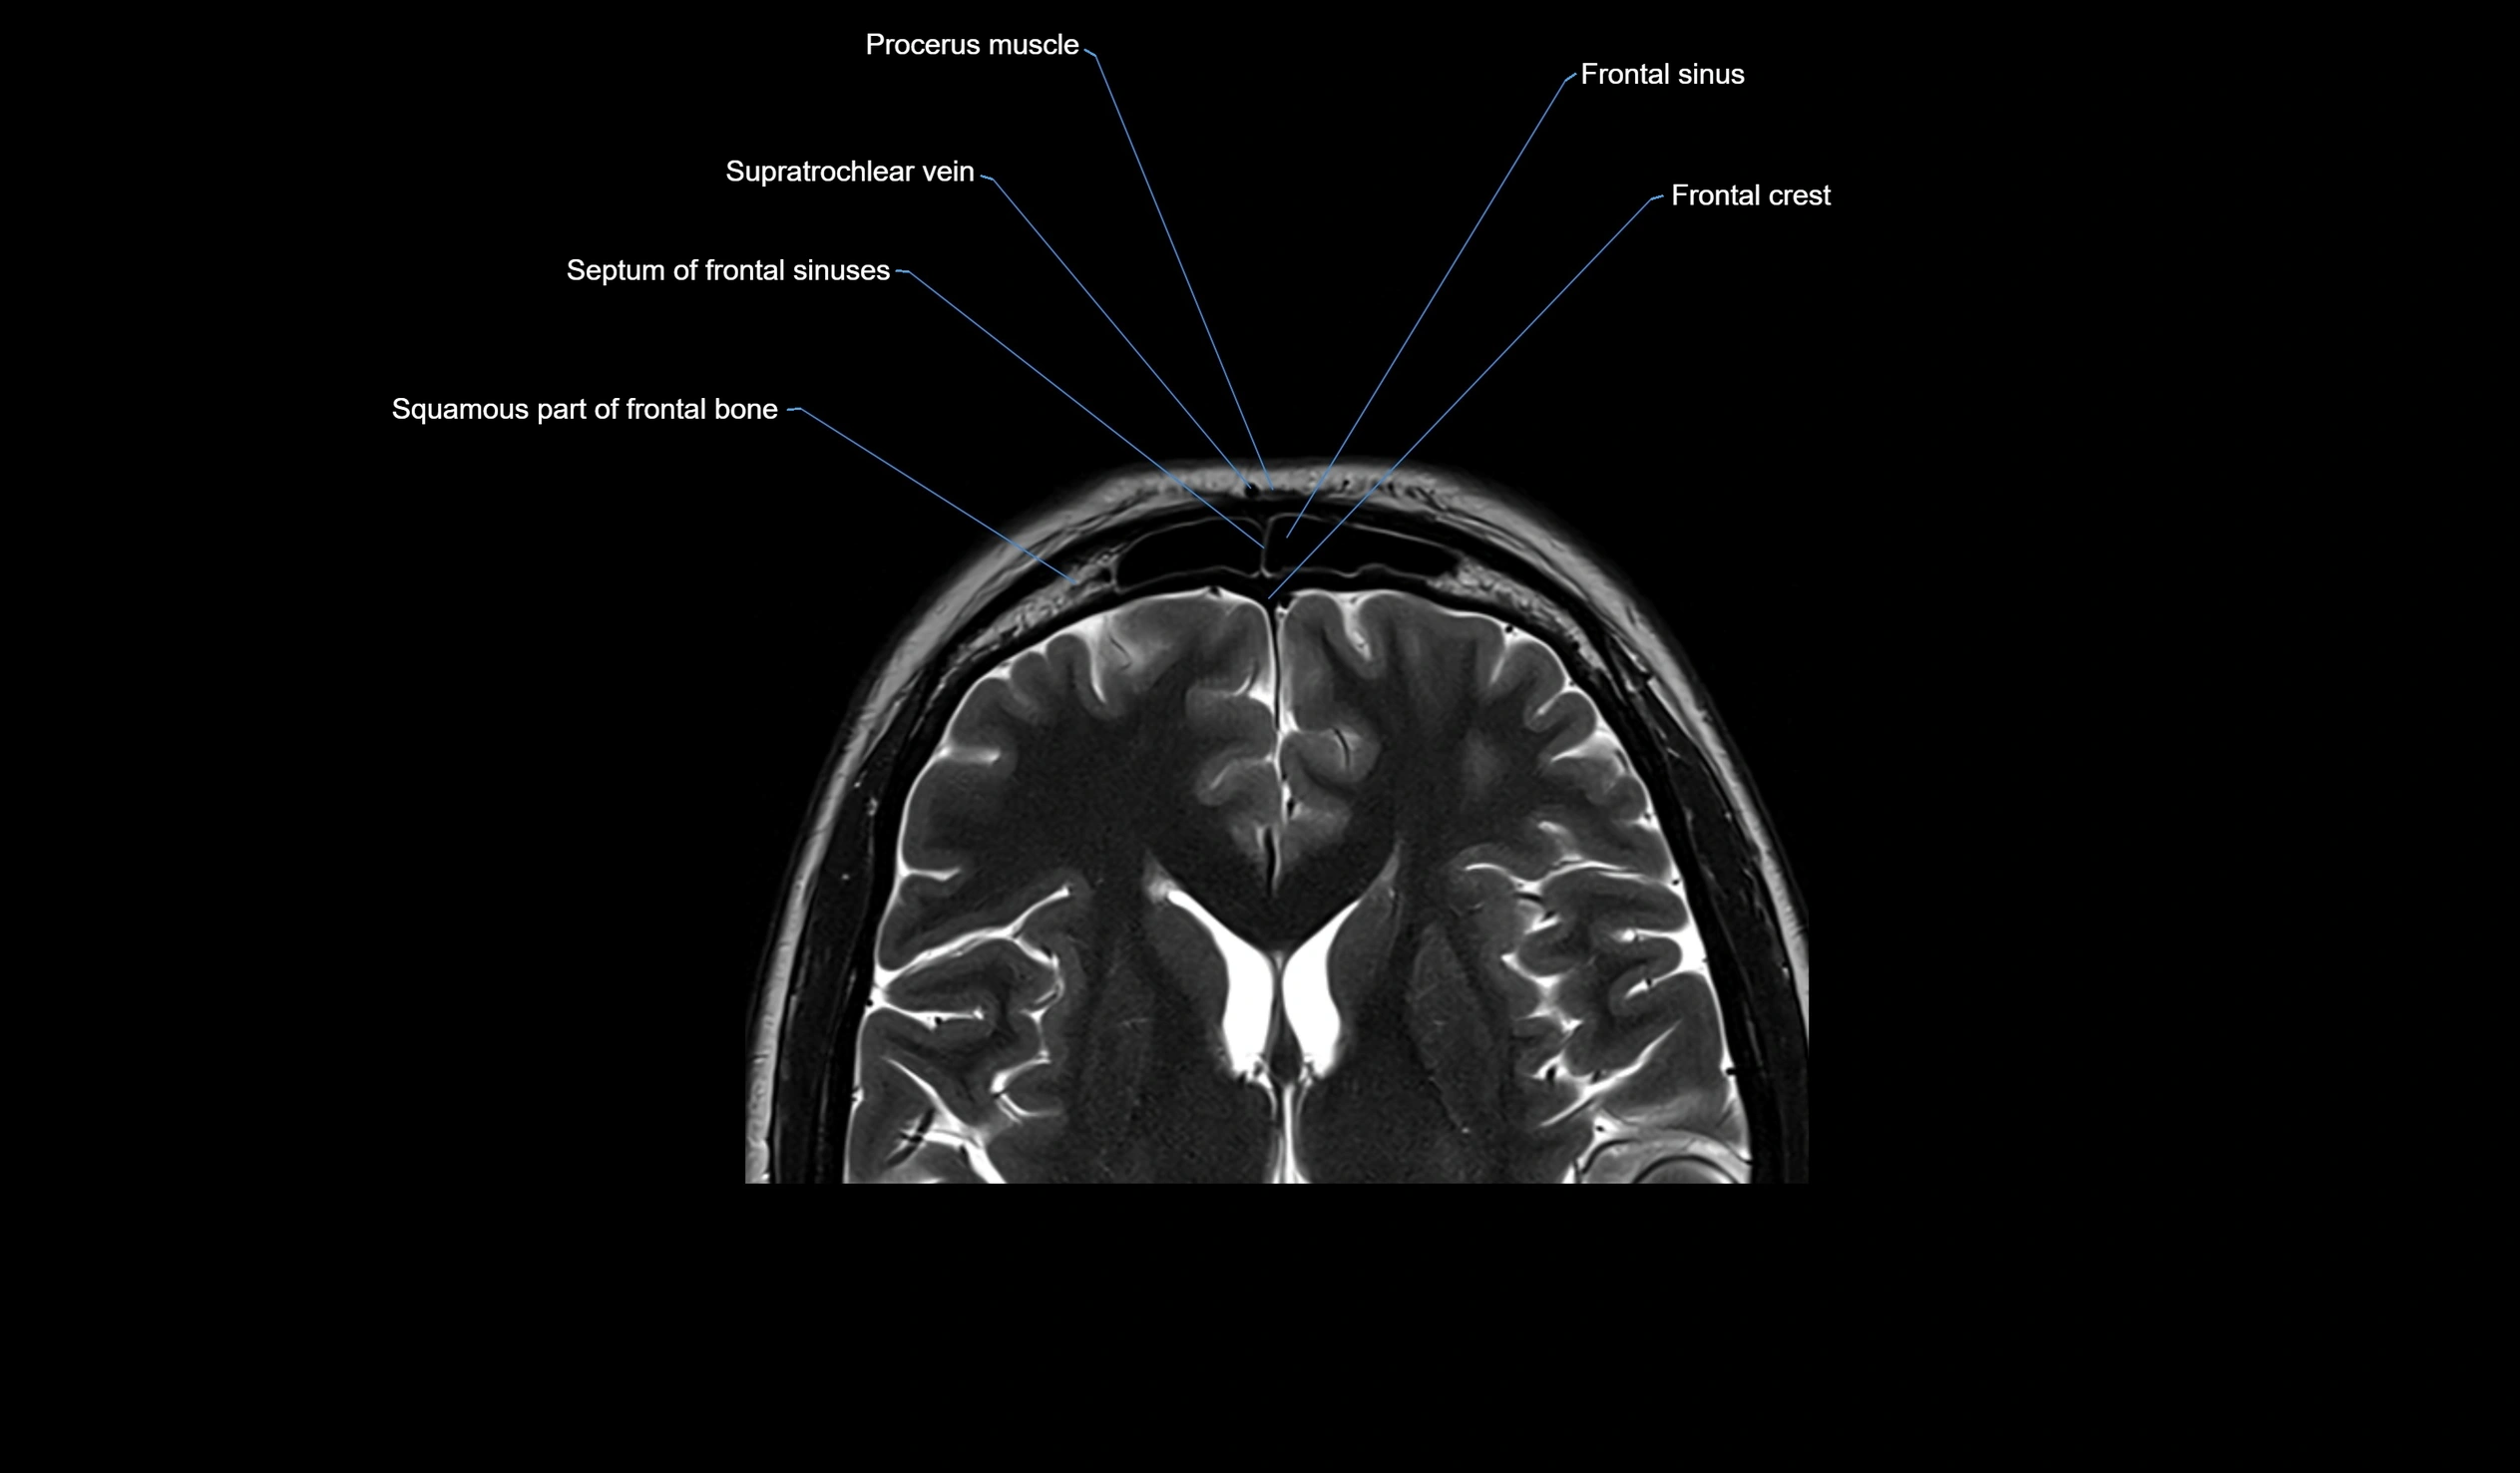

- Frontal sinus

- Supratrochlear vein